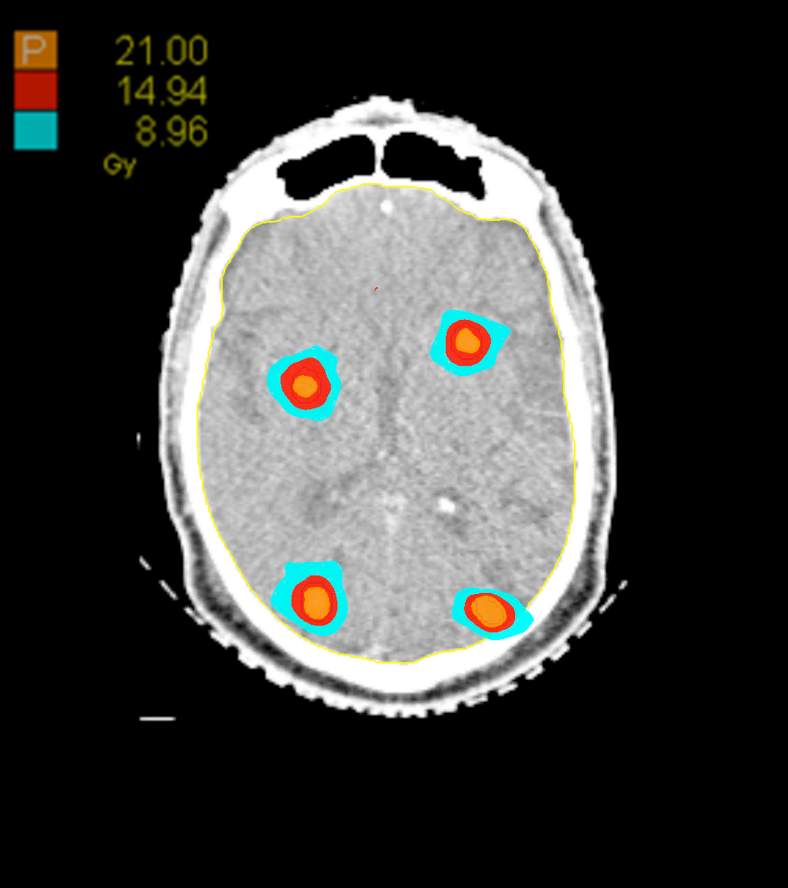

Treatment Plan Images

Dose Distributions

- Prescription to the 70.3% isodose line

- Max. dose 29.9 Gy